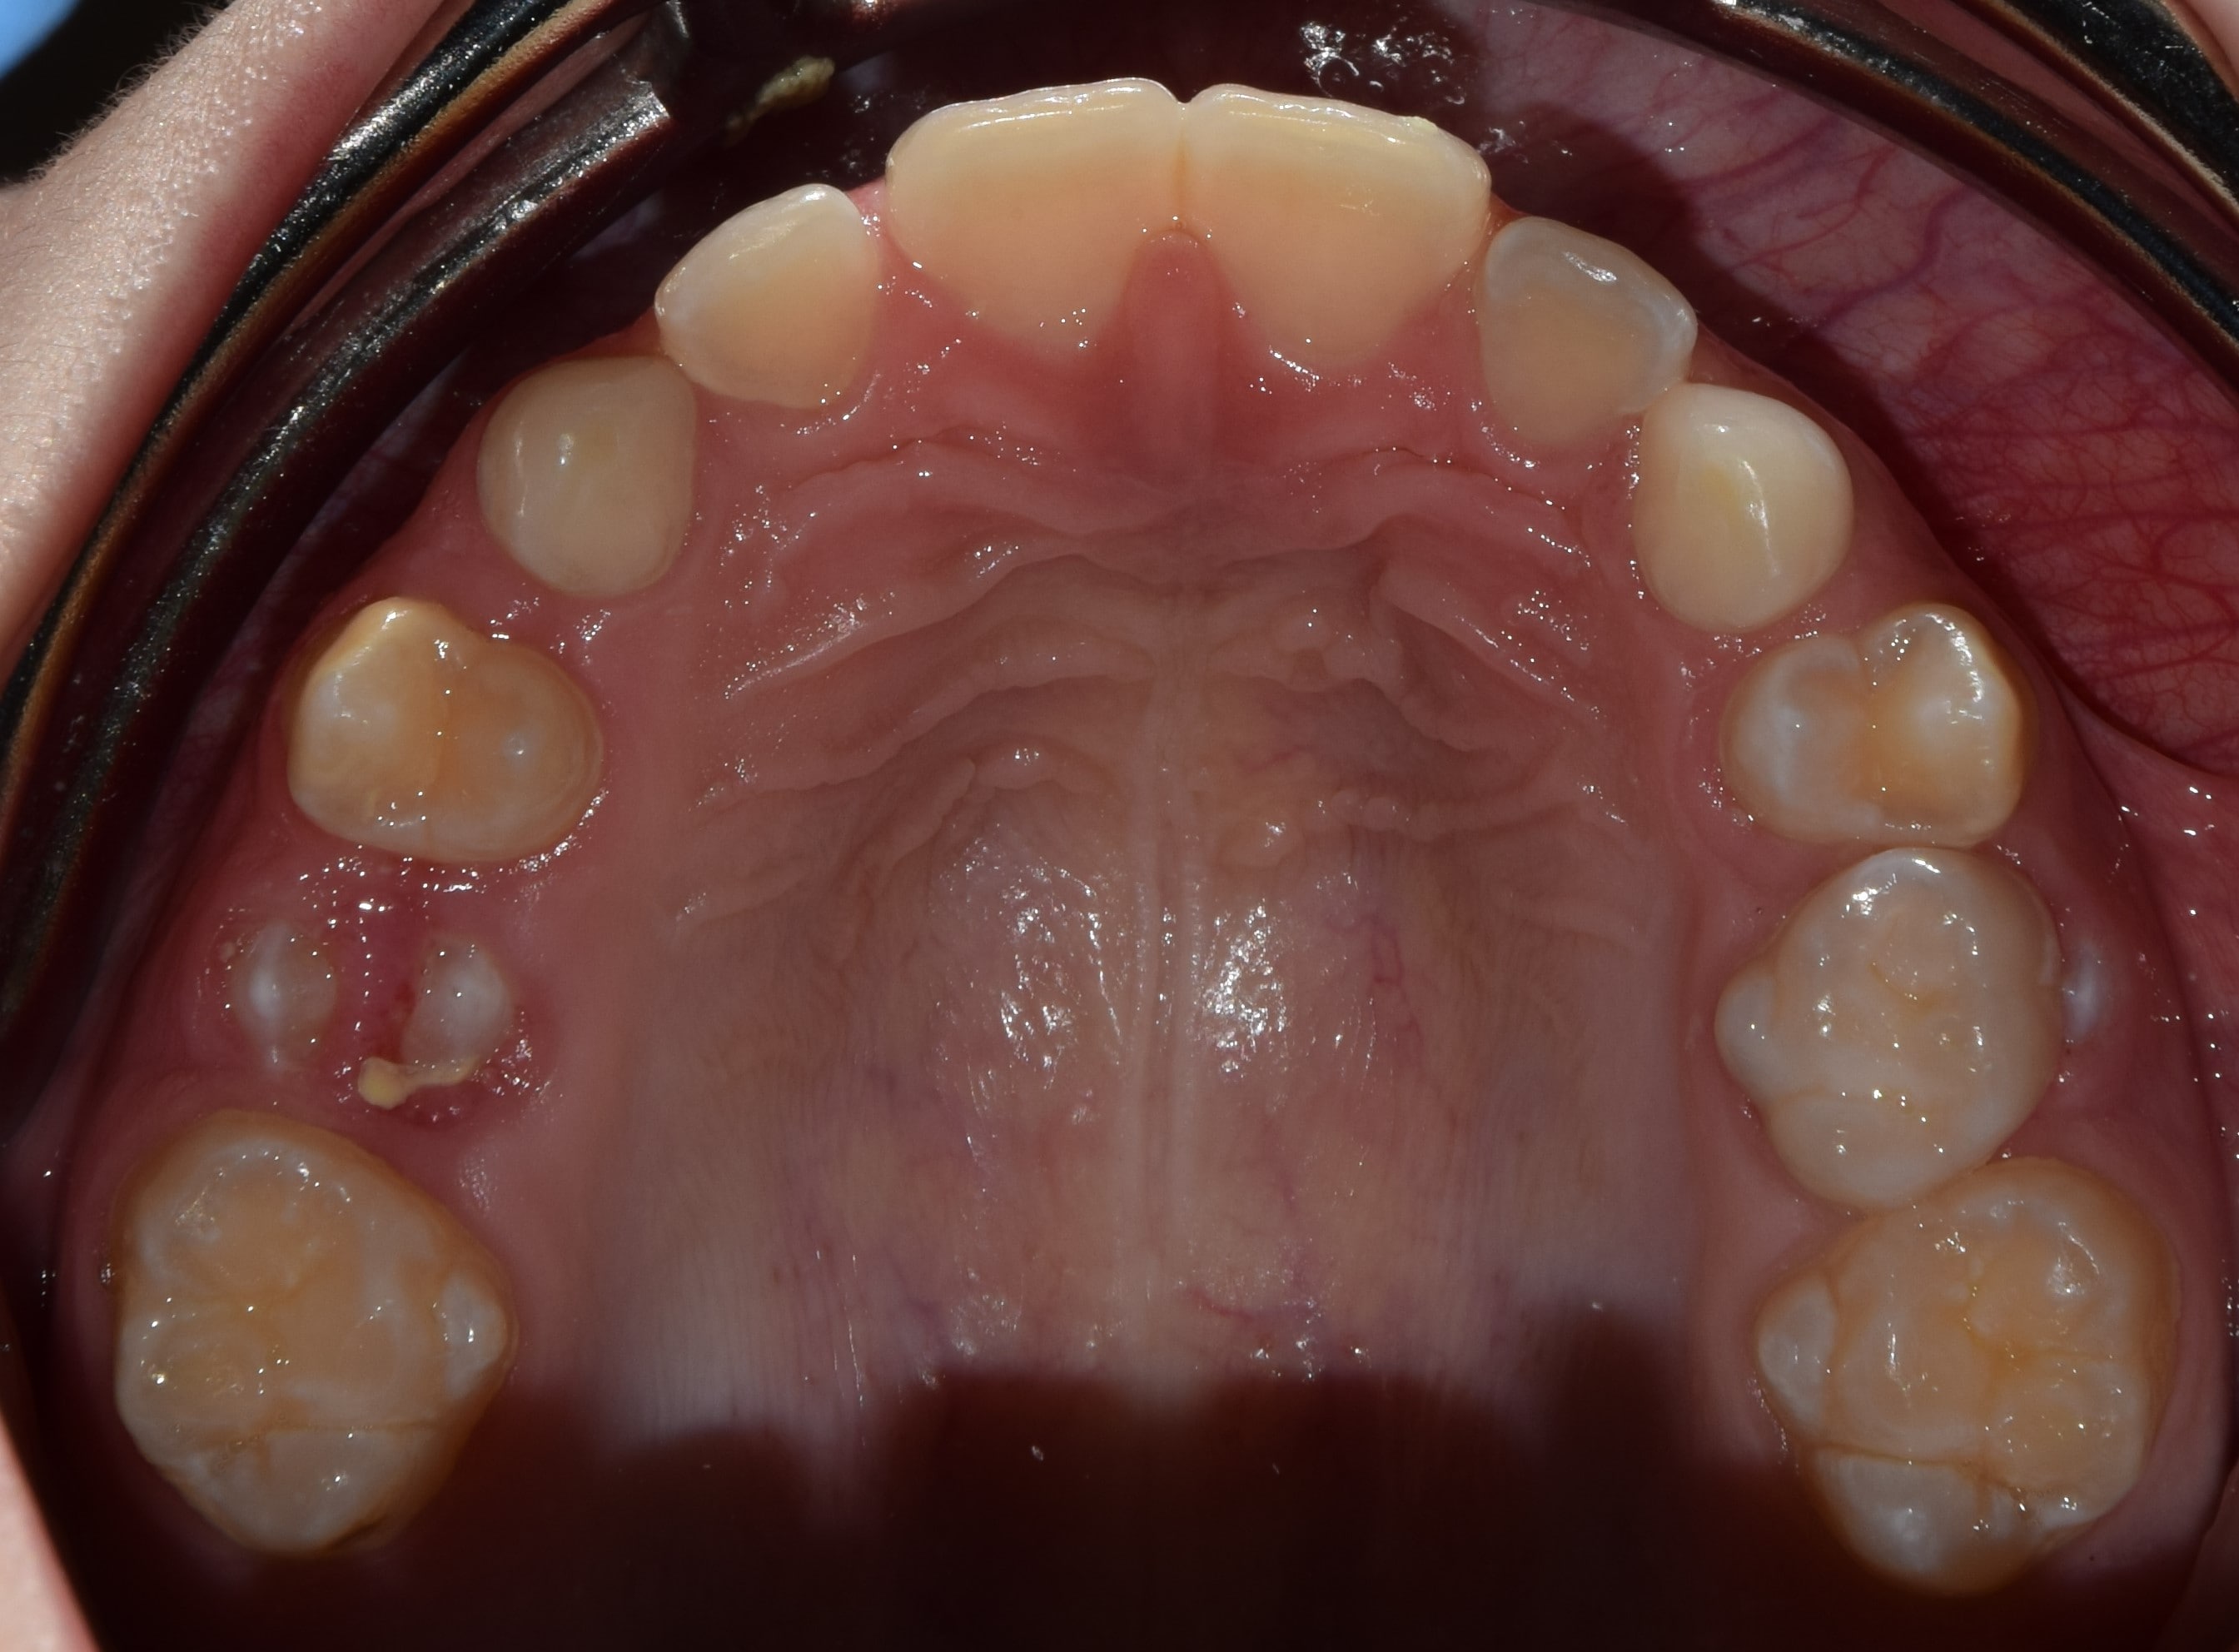

A fogszabályzó kezelés előtt-alatt-után rendszeresen készítünk fényképeket. Ez egy külön erre a célra összeállított tükörreflexes fényképezőgéppel történik. Nem a legkellemesebb élmény a fogszabályozás során, de utána nagyon jó lesz visszanézni a képeket. Sok fontos információt nyerhetek ki a készített fotókból, olyanokat is, amelyeket esetlegesen szájban nem veszek észre (nagyon kis méretűek), de egy nagy monitoron már könnyedén. A fotódokumentáció tehát még pontosabbá, precízebbé teszi a kezeléseim, és segít a maximum elérésében.